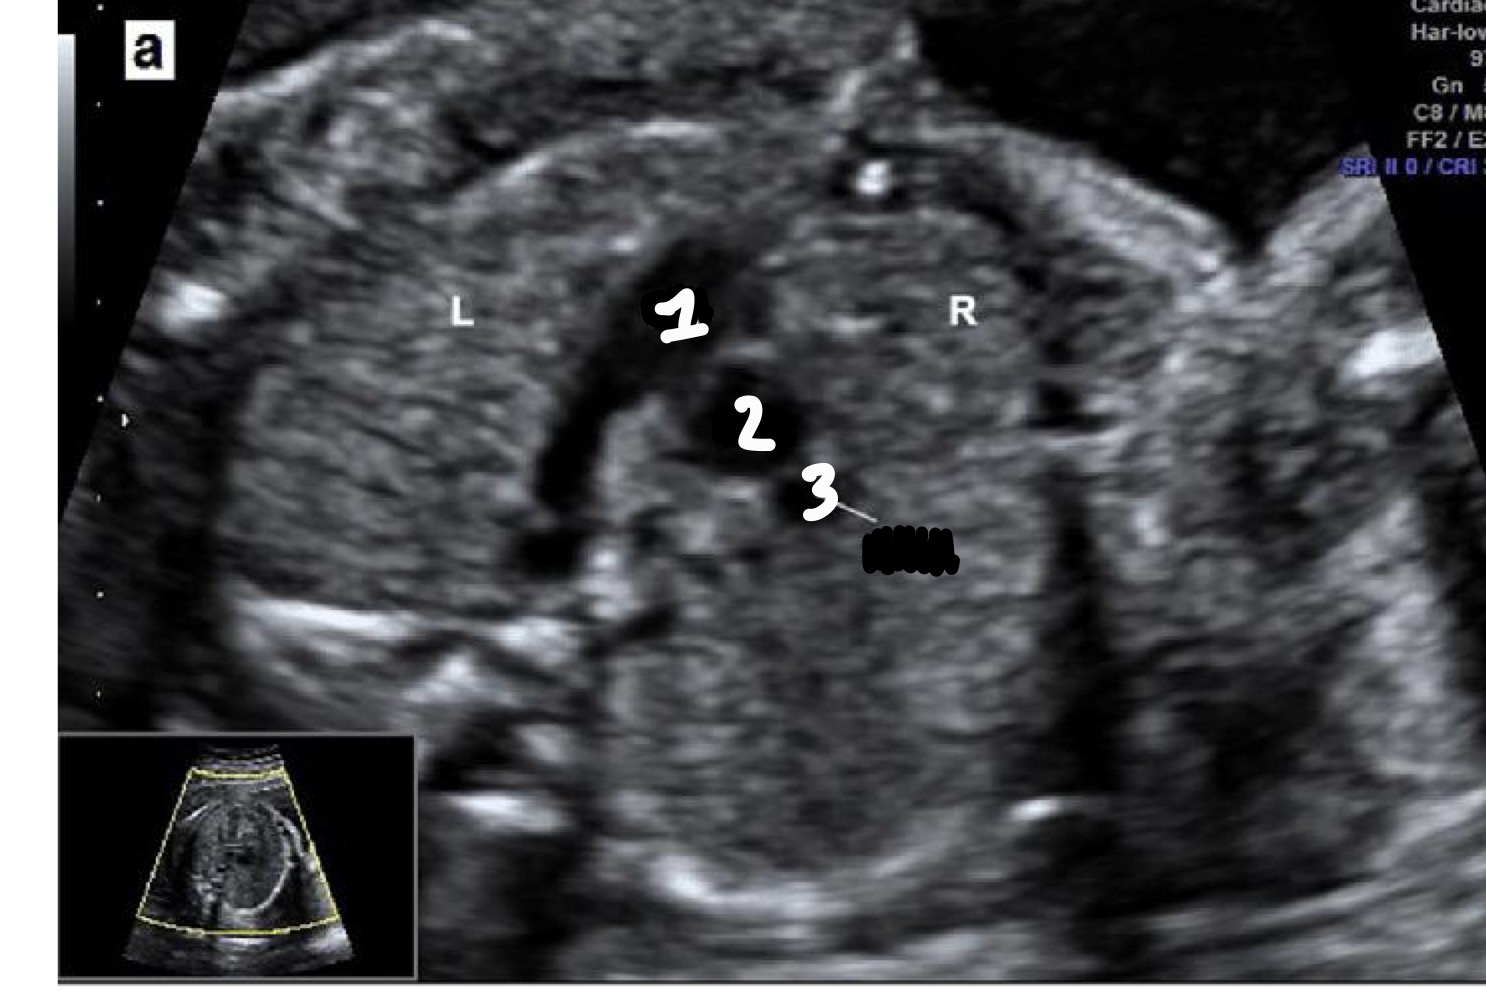

What view is this?

5 Chamber view

What additional structure is seen in the 5-chamber view

Aorta arising from the left ventricle

What is the purpose of the 5-chamber view

Evaluate aortic root and interventricular septum

Right ventricle

Left ventricle

Right atrium

Aorta

Left atrium

Descending aorta